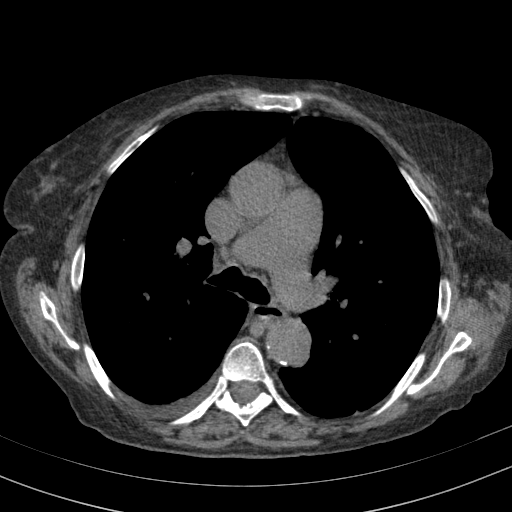

Original NATIVE CT scan (input)

Full window (WL 1023.5, WW 4095 β†’ Low βˆ’1024, High +3071)

Actual HU range: [-160.0, 240.0]